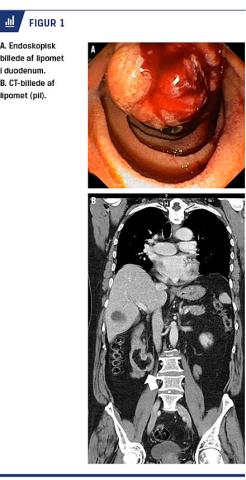

Patienten havde syv år tidligere haft samme symptomer, hvor man fandt ulcus. Han var i blodfortyndende behandling med clopidogrel pga. en tidligere apopleksi. Ved gastroskopi så man gastritis, ingen aktiv blødning fra de skoperede dele af mave-tarm-kanalen samt en mellemstor ulcereret tumor ved papilla duodeni major (Figur 1A). På grund af tumorens lokalisering rejstes der mistanke om malignitet. Der blev taget biopsier af tumoren i duodenum, planlagt CT og henvist til lever-pancreas-konference på Rigshospitalet.

De første biopsier viste uspecifik inflammation uden malignitet. CT’en bekræftede det endoskopiske fund, en 3 × 2 cm uregelmæssig proces i duodenum med fedtkomponent. Der var ingen tegn på intra- eller ekstrahepatisk galdestase (Figur 1B).